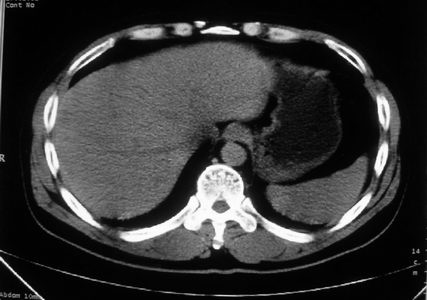

男,体查发现右肝低密度,右肾高密度结节影。高密度ct值92hu,囊肿?

肝右叶囊肿或血管瘤?右肾高密度囊肿。建议增强。

考虑肝右叶囊肿,右肾高密度囊肿;建议行ct增强扫描检查。

肝右叶囊肿或血管瘤?右肾高密度囊肿。还是增强后在对比观察较好,建议增强。